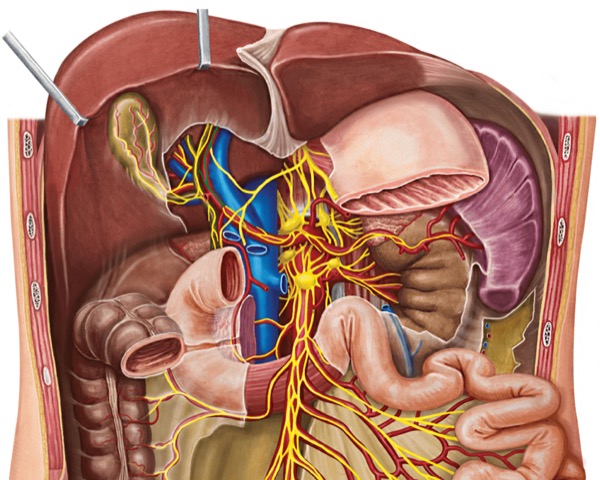

“And while we often address somatic pain effectively using local anesthesia and transversus abdominal plane blocks, visceral pain is traditionally ignored or treated with narcotics, which come with a host of adverse effects,” he continued. “In the case of foregut surgery, the sympathetic and parasympathetic nervous system is mediated through the celiac ganglia, which supplies the visceral sensory fibers to organs like the stomach, pancreas, liver and esophagus. So, I began to wonder if we can anesthetize or block this relay station, possibly stopping the visceral pain cycle.”

Dr. Sharma performs the block under general anesthesia. After standard port placement in the patient’s abdominal cavity, he incises the peritoneum close to the celiac trunk, where he exposes and identifies three to four ganglia. Using a dedicated probe, he injects 5 to 10 ml of the solution, depending on the size and number of ganglia.

“The ganglia are sitting on top of the aorta, so you have to be careful with the injection,” he said. “Many patients will experience a drop in blood pressure during surgery, so you have to make sure they’re well hydrated beforehand.